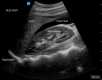

The diagnostic evaluation of ectopic pregnancy primarily relies on the assessment of serum beta-human chorionic gonadotropin (β-hCG) levels in conjunction with imaging modalities such as transvaginal ultrasonography (TVUS) and transabdominal ultrasonography (TAUS). Among these, TVUS has been demonstrated to be the most sensitive and accurate for early detection of ectopic pregnancy, particularly when enhanced with 3-dimensional imaging and color Doppler ultrasound (seeImage. Ectopic Pregnancy).[4]

TVUS is the gold standard for diagnosing ectopic pregnancy, with definitive confirmation when a yolk sac or embryo is visualized outside the uterus (seeImage. Ectopic Pregnancy, Ultrasound). However, many cases may not continue to develop to this point, necessitating additional diagnostic approaches, including serial β-hCG monitoring, repeat ultrasonography, and uterine aspiration. In cases where neither an IUP nor an ectopic pregnancy is identified, the pregnancy is categorized as a pregnancy of unknown location (PUL). In such cases, serial β-hCG monitoring and, in some instances, manual vacuum aspiration can help differentiate between a failing IUP and an ectopic pregnancy.[1][6]

Ectopic Pregnancy, Ultrasound. This ultrasound image reveals an ectopic pregnancy. Contributed by K Ghaffarian, DO